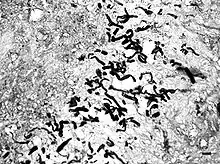

Pythiosis is suspected to be heavily underdiagnosed due to unfamiliarity with the disease, the rapid progression and morbidity, and the difficulty in making a diagnosis. Symptoms often appear once the disease has progressed to the point where treatments are less effective. As the organism is neither a bacterium, virus, nor fungus, routine tests often fail to diagnose it. In cytology and histology, the organism does not stain using Giemsa, H&E, or Diff-Quick, but the hyphae are outlined by surrounding tissue. GMS staining is required to identify the hyphae in slides, and highlights the lack of septation which helps distinguish the organism from fungal hyphae. Granulomatous inflammation with numerous eosinophils is suggestive that the hyphae are oomycetes rather than fungi, which are less likely to attract eosinophils. The symptoms are usually nonspecific and the disease may not be included in a differential diagnosis in human medicine, though it is familiar to veterinarians.